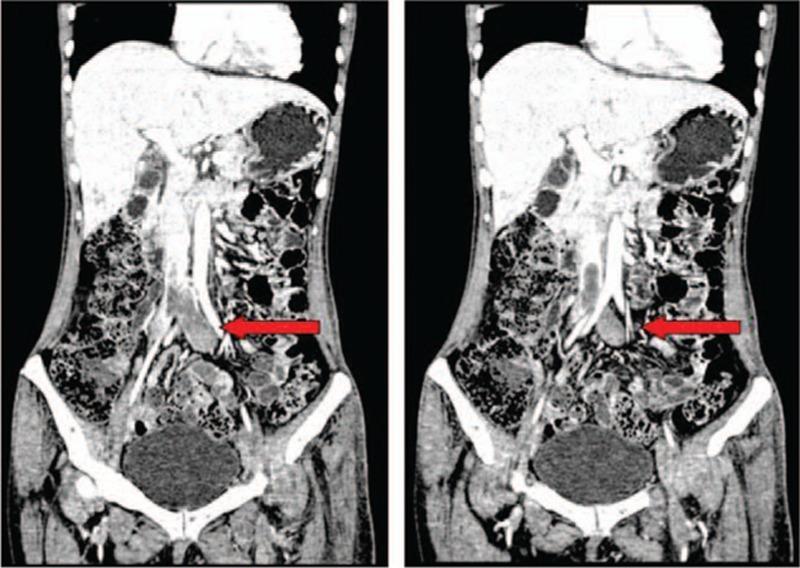

Hypereosinophilic syndrome (HES) can be fatal, particularly when eosinophils infiltrate vital organs and/or if extensive thrombosis develops. However there are no standard recommendations for the use of anticoagulant therapy of HES in the setting of thrombosis.

METHODS

We herein present a case of a 46-year-old female who presented with marked peripheral eosinophilia with symptoms of multi-organ infiltration and extensive deep venous thrombosis (DVT). In this case, evaluation was carried out before the diagnosis was established, and timely standard-dose corticosteroids combined with a new oral anticoagulant (NOAC) therapy were carried out.

RESULTS

These measures resulted in a rapid response and long-term disease control.